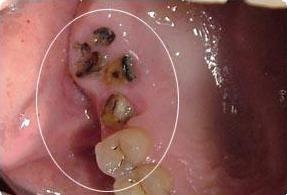

首先科普一下什么是残根。我们把一颗牙齿比作一颗"大树",牙科疾病好似"虫子",一直在不断攻击牙齿这颗"大树",最后只剩下树根。我们通常把这种残缺程度的牙齿称为残根。

对于残根的去留问题,主要是基于两方面的考虑。一方面是患牙是否有炎症,炎症是否可以通过控制和治疗来维护口腔健康;另一方面是患牙经过治疗后能否恢复功能,像残根过短不能利用也是要拔除的。

不管最终决定要不要残根,残根一定不要放任不管。残根使牙齿的髓腔、根管暴露于口腔充满细菌的环境中,进一步还可以引起全身的其它疾病。

牙根残缺会导致食物嵌塞,清洁不到位造成细菌感染,诱发牙龈炎、龋齿等一系列牙科疾病。最严重的情况牙齿出现松动,一旦咀嚼硬物容易崩牙或脱落。

残根会不定期刺激摩擦损伤口腔内的粘膜,会让娇嫩的口腔粘膜吃不消,容易形成创伤性溃疡。同时也大大提高了患癌风险,易引发舌癌、口腔癌等后果。